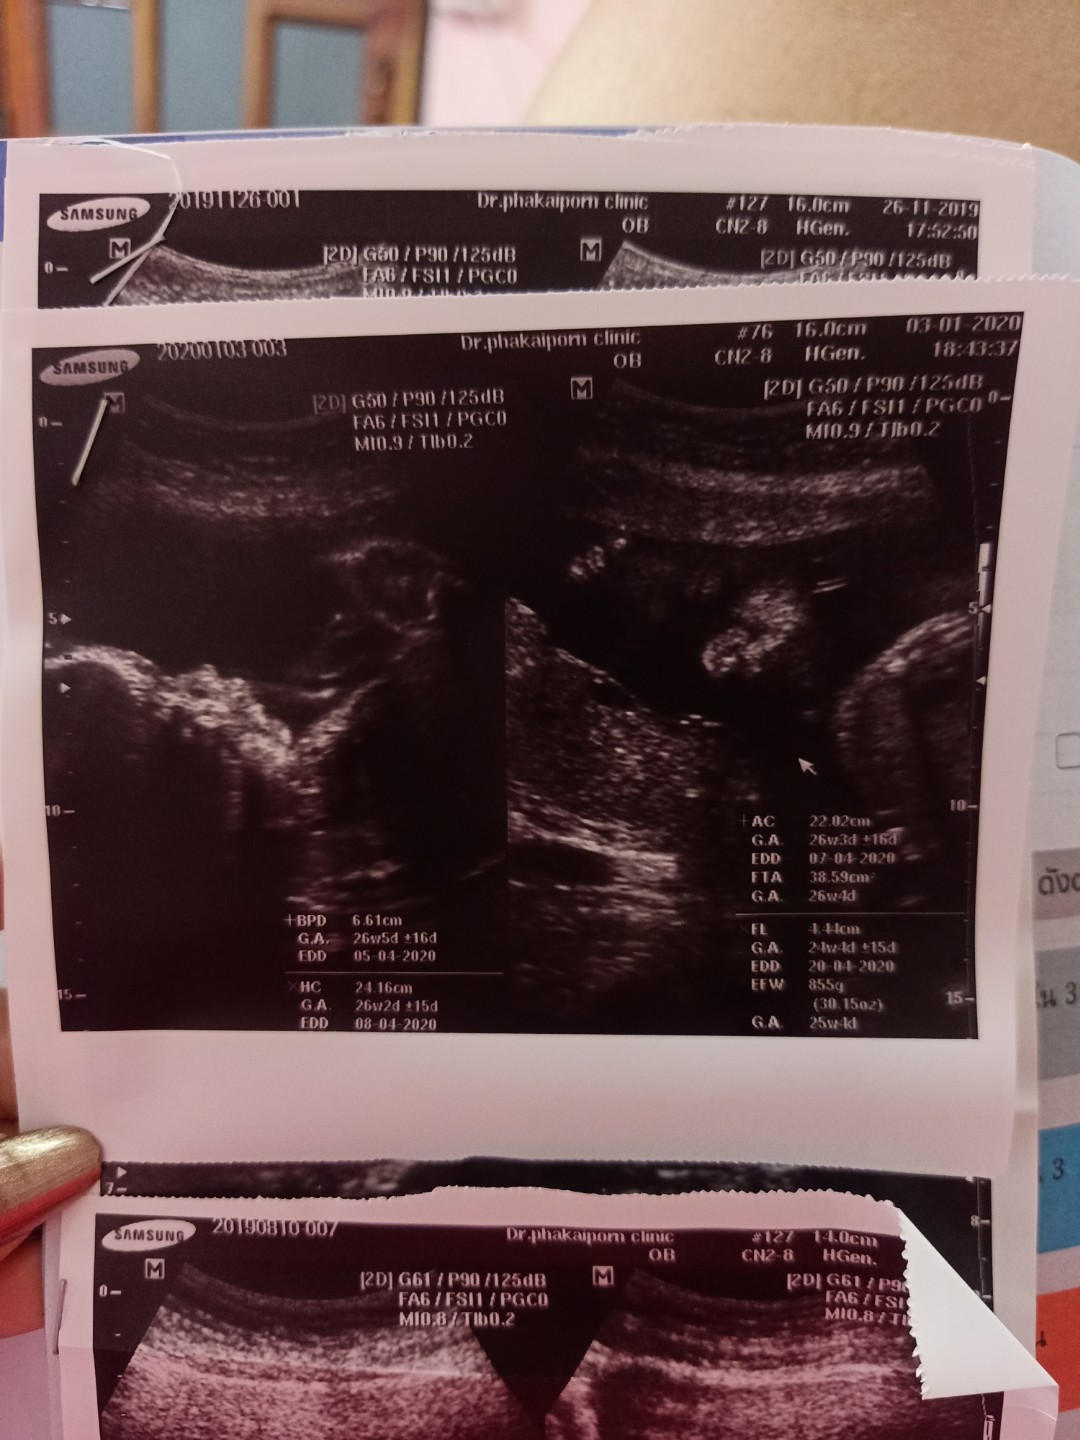

ผู้หญิงค่ะ